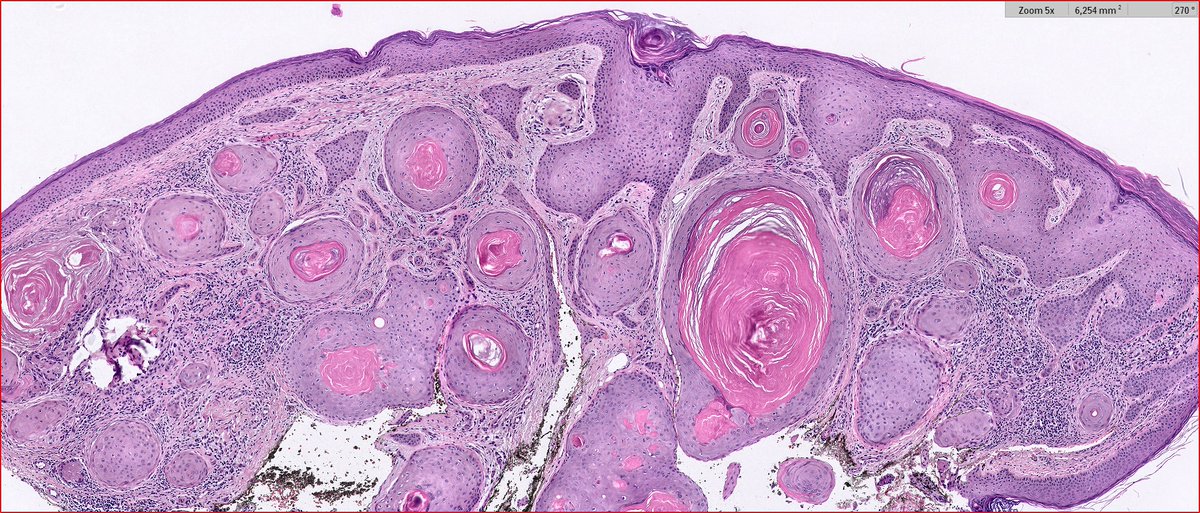

2024 Wk46 ish! RAC9183. M80s Right temple lesion. Previous skin cancers. #TooFarToDiagnose ? #Dermpath